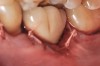

Problem: The implant is placed too facially, and there is significant labial gingival recession, contour change, and mucosal discoloration around the implant, abutment, and crown (Figure 3 and Figure 4). The implant attachment apparatus is intact and healthy, but the patient has a thin periodontal phenotype.

Fig 3. A patient presented with a high smile line and midfacial recession of the maxillary right lateral incisor as evidenced by the increased tooth length compared with the contralateral lateral incisor.

Fig 4. Intraoral view of tooth No. 7 with the gingival zenith more apical than the adjacent central incisor and canine tooth.